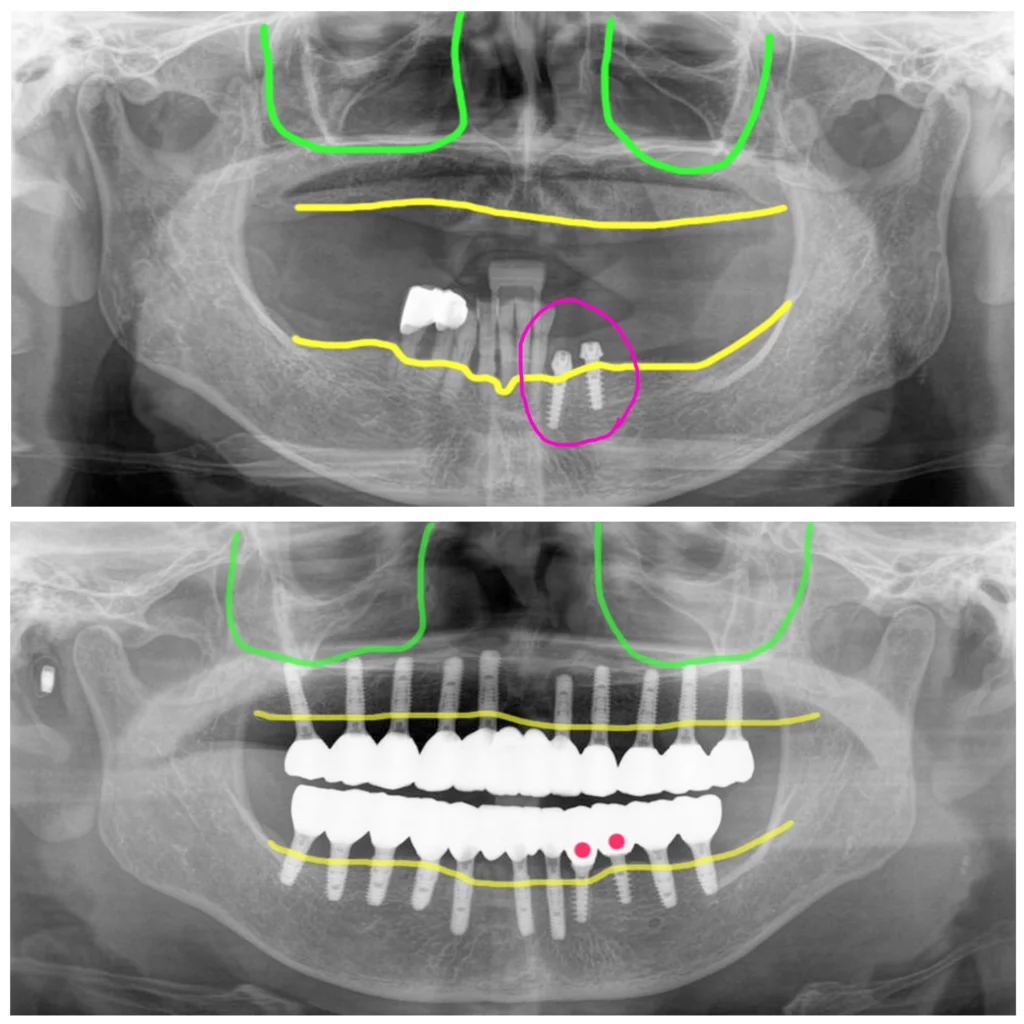

위쪽에는 치아가 하나도 없이 10년 이상 틀니를 사용했고 아래에는 치아가 다수 남았지만 치조골이 모두 내려가 제거 후 전체임플란트로 계획을 했습니다.

왼쪽 아래에는 본원에 오시기 전에 임플란트 2개를 심어 두셨는데 치료가 너무 길어져 빠른 치료를 원하셨어요.

골폭이 좁고, 골질이 낮아서 초기고정을 얻기에 어려움이 있었지만 조심스럽게 수술을 진행해서 위에 10개, 아래 9개 식립했습니다. 식립한 지대주에 수술당일 임시치아를 만들어 드렸구요.

이런 경우에는 아무래도 골질이 좋은 분 보다는 골융합이 이루어지는 동안의 식사를 좀 더 조심해야 합니다. 이 분은 식이를 잘 조절해 주셔서 실패없이 모든 임플란트가 잘 고정이 되어 최종 보철을 이렇게 마무리했습니다.

이렇게 해서 이 환자는 총 4회 방문 총 치료기간 4개월로 전체임플란트 치료를 완료했습니다. 수술, 실밥, 스캔, 세팅으로 방문하셨습니다.

타병원에서 식립한 임플란트도 같이 이용해서 앞니, 어금니 이렇게 나누어 몇 개의 임플란트들을 연결하는 방식의 지르코니아 보철을 완성했습니다.